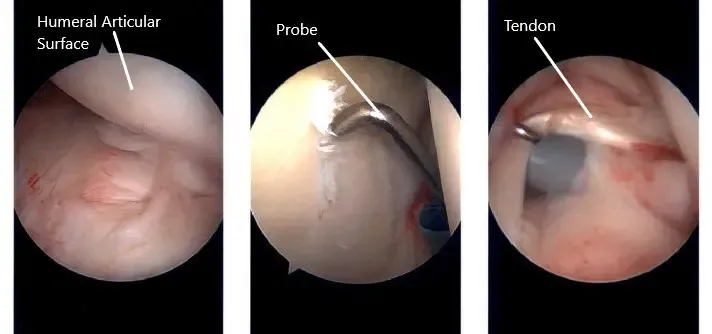

Se realizó el portal de entrada posterior para el hombro y se introdujo el endoscopio en la articulación glenohumeral. La entrada al portal anterior se realizó mediante una aguja espinal a través del intervalo rotador y se insertó una cánula. La sonda se utilizó examinando el hombro y se encontró una osteoartritis leve, de grado 1 a grado 2 del centro de la superficie glenoide.

Hubo desgarros parciales en el subescapular superior, que fue desbridado. Había una tendinitis leve en el tendón del bíceps, pero no se desgarró y no se hizo nada al respecto. Se observó una rotura completa del manguito rotador en el supraespinoso e infraespinoso del hombro. Se deshilachó el labrum glenoideo, que fue desbridado con la afeitadora. El resto del examen del hombro fue normal.

Imágenes artroscópicas intraoperatorias del hombro izquierdo.

El endoscopio se introdujo por el portal anterior para confirmar los hallazgos. Ahora, el alcance se introdujo en el espacio subacromial. El examen mostró bursitis, que fue desbridada con la afeitadora. Se encontró una gran ruptura del supraespinoso e infraespinoso.